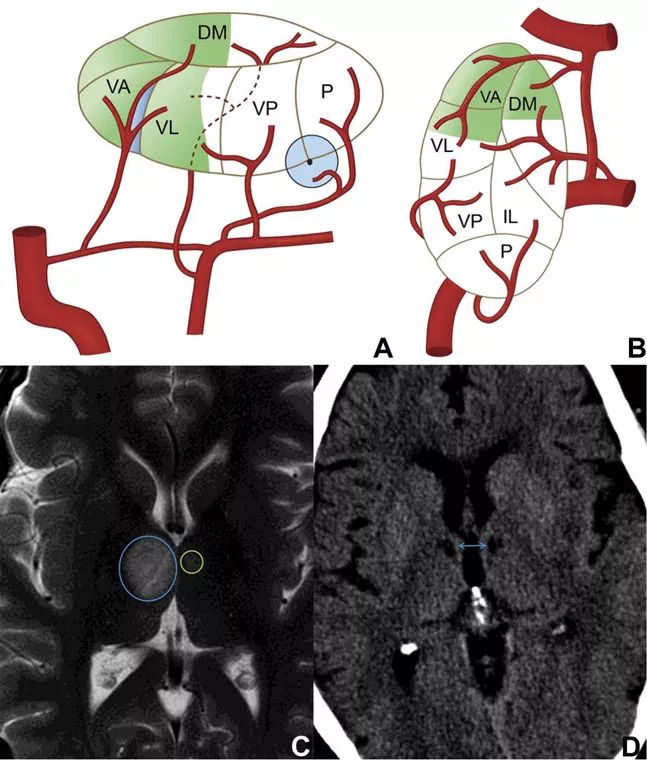

图3 丘脑结节动脉供血示意图和梗死影像学表现

丘脑前部区域由丘脑结节动脉供血,该动脉起源于后交通动脉的中部1/3处,这与源自PCA的其他丘脑动脉区域不同。该部位的梗死临床特征很明显,主要表现为严重和广泛的神经心理缺陷。

该部位梗死早期可表现出不同程度的意识水平改变和沉默寡言,持续的人格变化则见于疾病的后期,包括时间和空间定位障碍、冷漠、缺乏自知力等,情感方面的障碍可能很明显。丘脑前部梗死的其他常见症状是顺行记忆障碍,以及伴有低频发音和构音障碍的失语症。